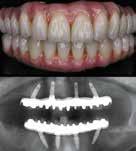

Dental implants available in Dr Oberai’s prestigious clinics in Wilmslow.

Consider dental implants if you have missing or loose teeth. All on 4 implants offer a permanent solution, especially for denture wearers or those with multiple failing teeth. This minimally invasive digitally planned procedure ensures comfort, confidence, and full arch restoration in a day. It involves using four to six implants surgically placed into the jawbone, followed by a temporary bridge for healing and a later permanent one.

To check suitability, book a free consultation with Dr. Nikhil Oberai through our friendly reception team.

‘Implant retained bridges and dentures can offer comfort and confidence’